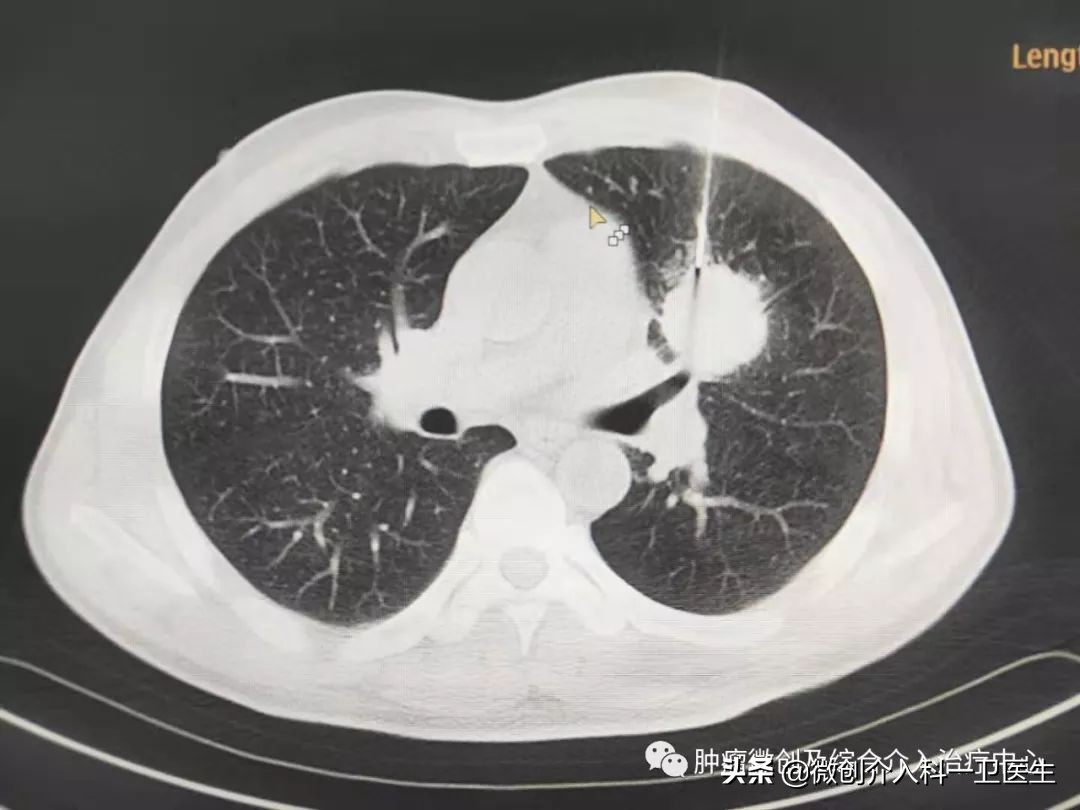

图1、2 局麻后在CT精确引导下经穿刺活检针穿刺进入肿瘤内部,创口约棉签样大小,取出长条形软组织,进行病理化验。

图 3. CT引导下穿刺过程。

图4、5、6. 引导下精准穿刺进入肿瘤内部穿刺图